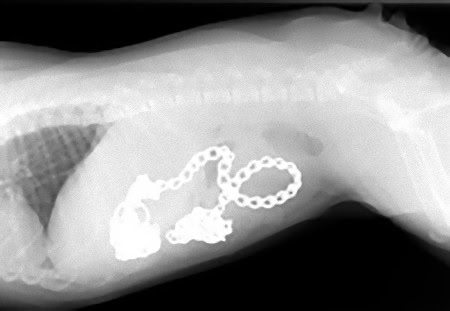

この画像を大きなサイズで見る6ヶ月のブルドッグ、トレーニング用チェーン